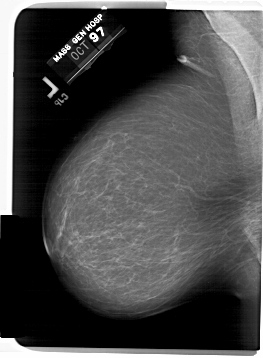

A_1583_1.RIGHT_CC

LEFT_CC LINES 6046 PIXELS_PER_LINE 4876 BITS_PER_PIXEL 12 RESOLUTION 43.5 NON_OVERLAY

LEFT_MLO LINES 6796 PIXELS_PER_LINE 4996 BITS_PER_PIXEL 12 RESOLUTION 43.5 NON_OVERLAY